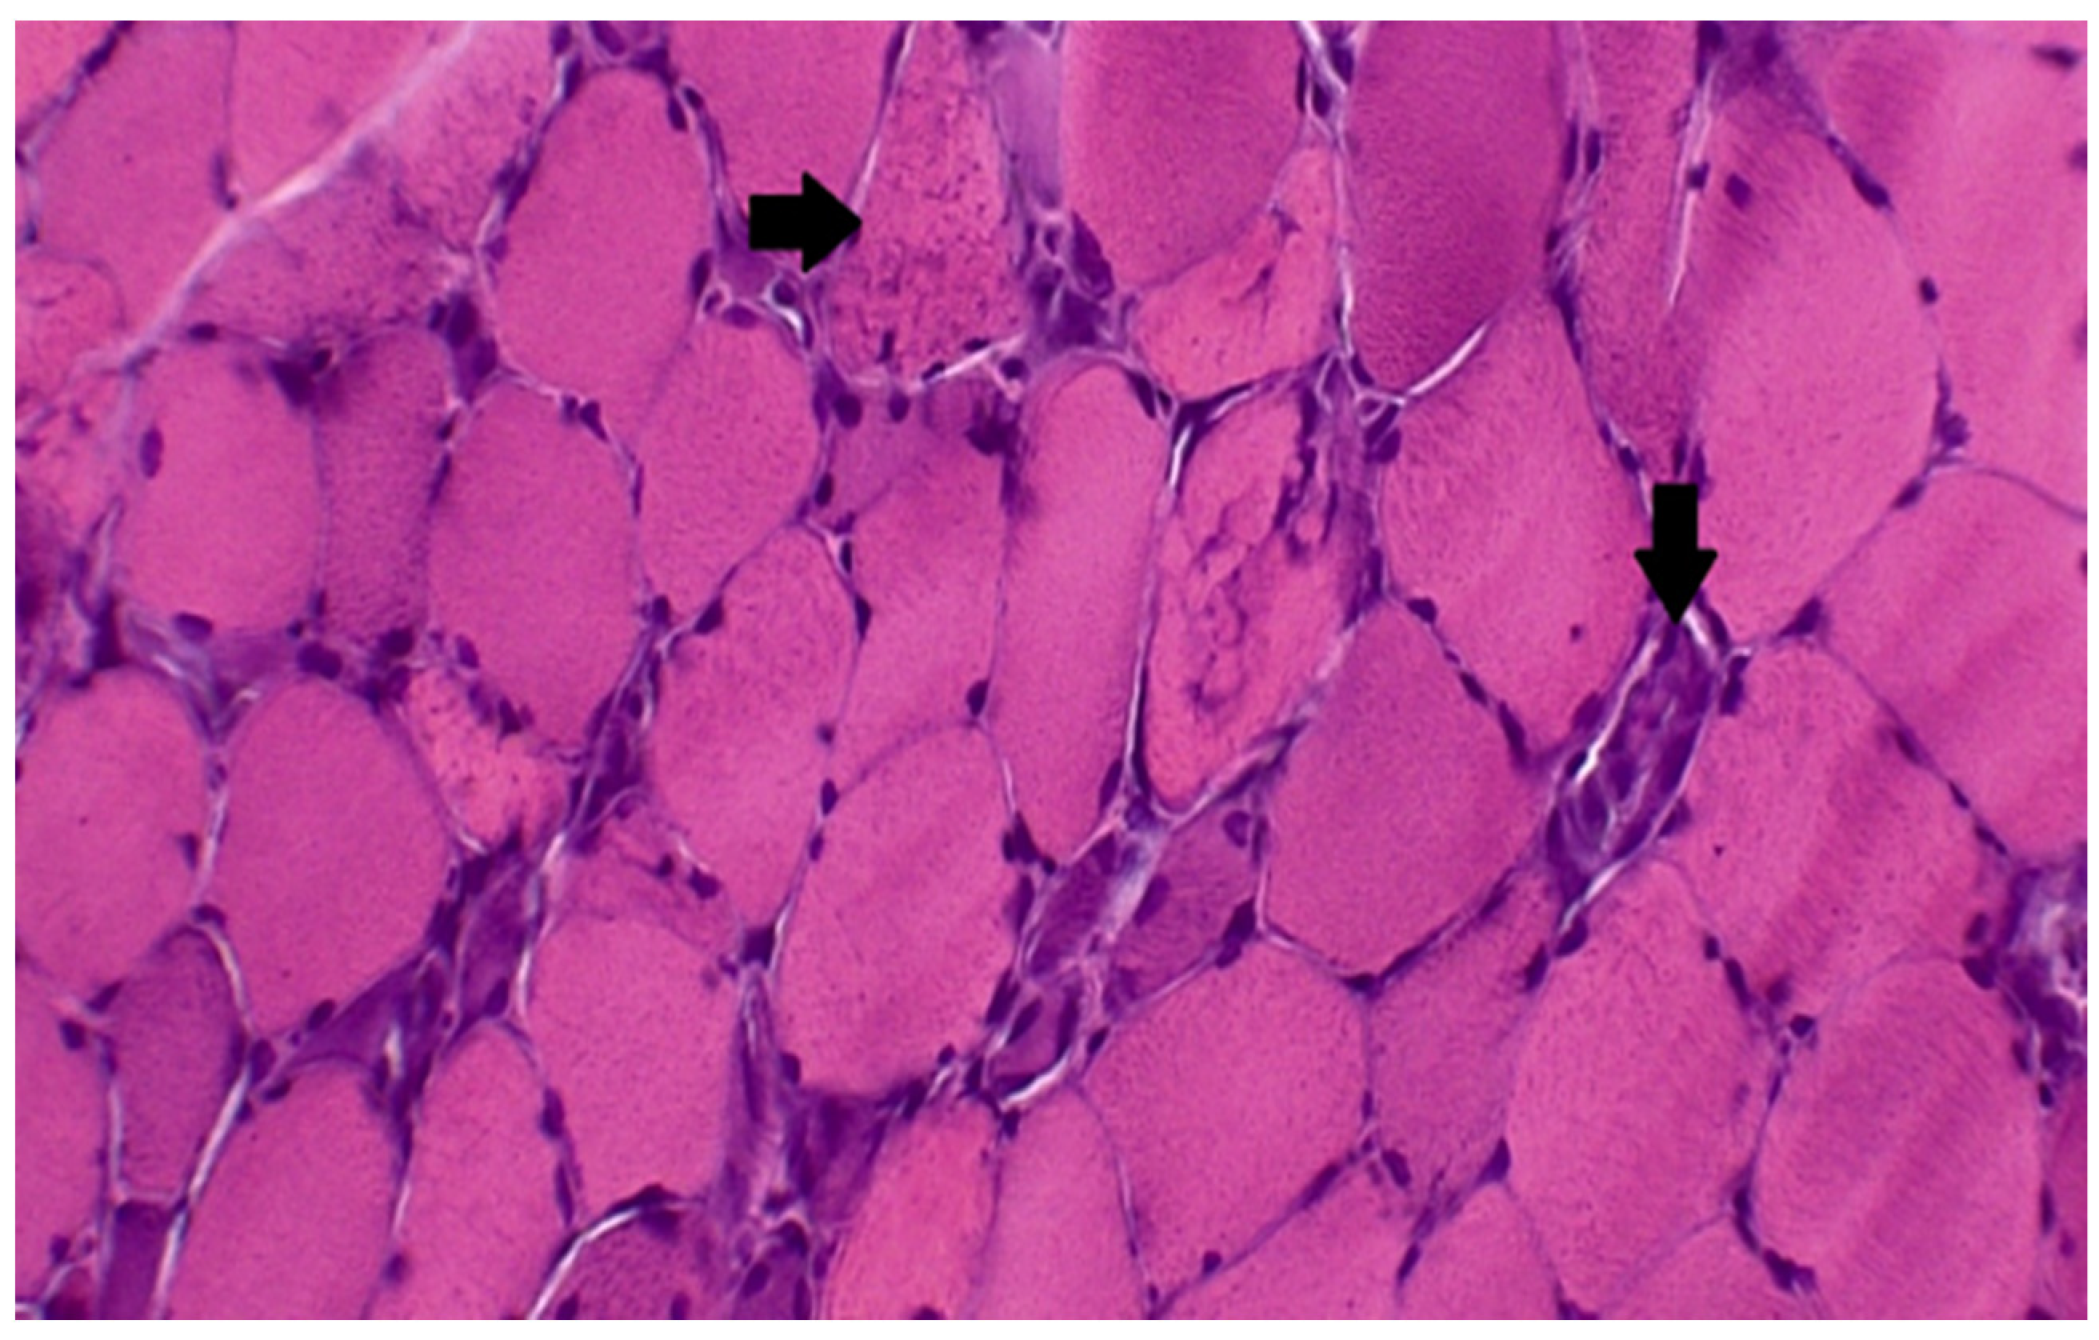

7.2. Immune-Mediated Necrotizing Myopathy Statin-Related

- Villa, L.; Lerario, A.; Calloni, S.; Peverelli, L.; Matinato, C.; DE Liso, F.; Ceriotti, F.; Tironi, R.; Sciacco, M.; Moggio, M.; et al. Immune-mediated necrotizing myopathy due to statins exposure. Acta Myol. 2018, 37, 257–262. [Google Scholar] [PubMed]

- Pinal-Fernandez, I.; Casal-Dominguez, M.; Mammen, A.L. Immune-Mediated Necrotizing Myopathy. Curr. Rheumatol. Rep. 2018, 20, 21. [Google Scholar] [CrossRef]

- Zaki, M.M.; Virk, Z.M.; Lopez, D.; Klubnick, J.; Ahrendsen, J.T.; Varma, H.; Kyttaris, V.; Abeles, I. A case of statin-associated immune-mediated necrotizing myopathy with atypical biopsy features. Eur. J. Rheumatol. 2021, 8, 36–39. [Google Scholar] [CrossRef]